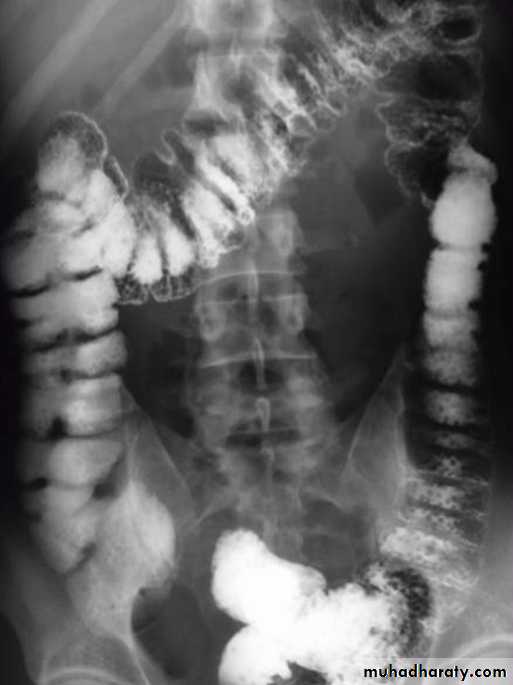

•Diverticular disease of the colon

• Due to over activity and hypertrophy of transverse bands of smooth muscle which result in increased intra-luminal tension with herniation of mucosa through week point in the wall.The condition is commonly seen in left hemi-colon.Radiological appearance:Plain film: show air trapping .• Ba. Enema :

• *Early appearance show saw-teeth colon (pre-diverticular stage).• *The diverticulum is consist of body and neck , best seen in post evacuation film .

• *Faecal impaction may result in incomplete filling of the body or flask shape .